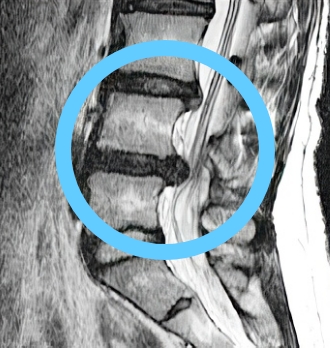

치료 후 탈출된 디스크

10년간 지속적 흡수

탈출된 디스크가 치료 후 10년간 지속적으로 감소, 10년 후에는 약 2/3 가까이 거의 흡수됨

비수술 한방통합치료 치료 10년 후

탈출된 디스크가 흡수된 모습

치료 전 (2007)

10년 경과 (2018)

※ 환자분에게 사전 동의를 받아 동일 조건에서 촬영되었으며, 개인에 따라 치료 후 부작용이 발생할 수도 있으니 의료진과 상담 후 치료를 진행하시기 바랍니다.

MRI상 디스크 흡수 확인

환자의 통증과 기능 평가 외, 10년에 걸친

MRI 검사를 통해 탈출된 디스크의 흡수와

근육량 증가 확인